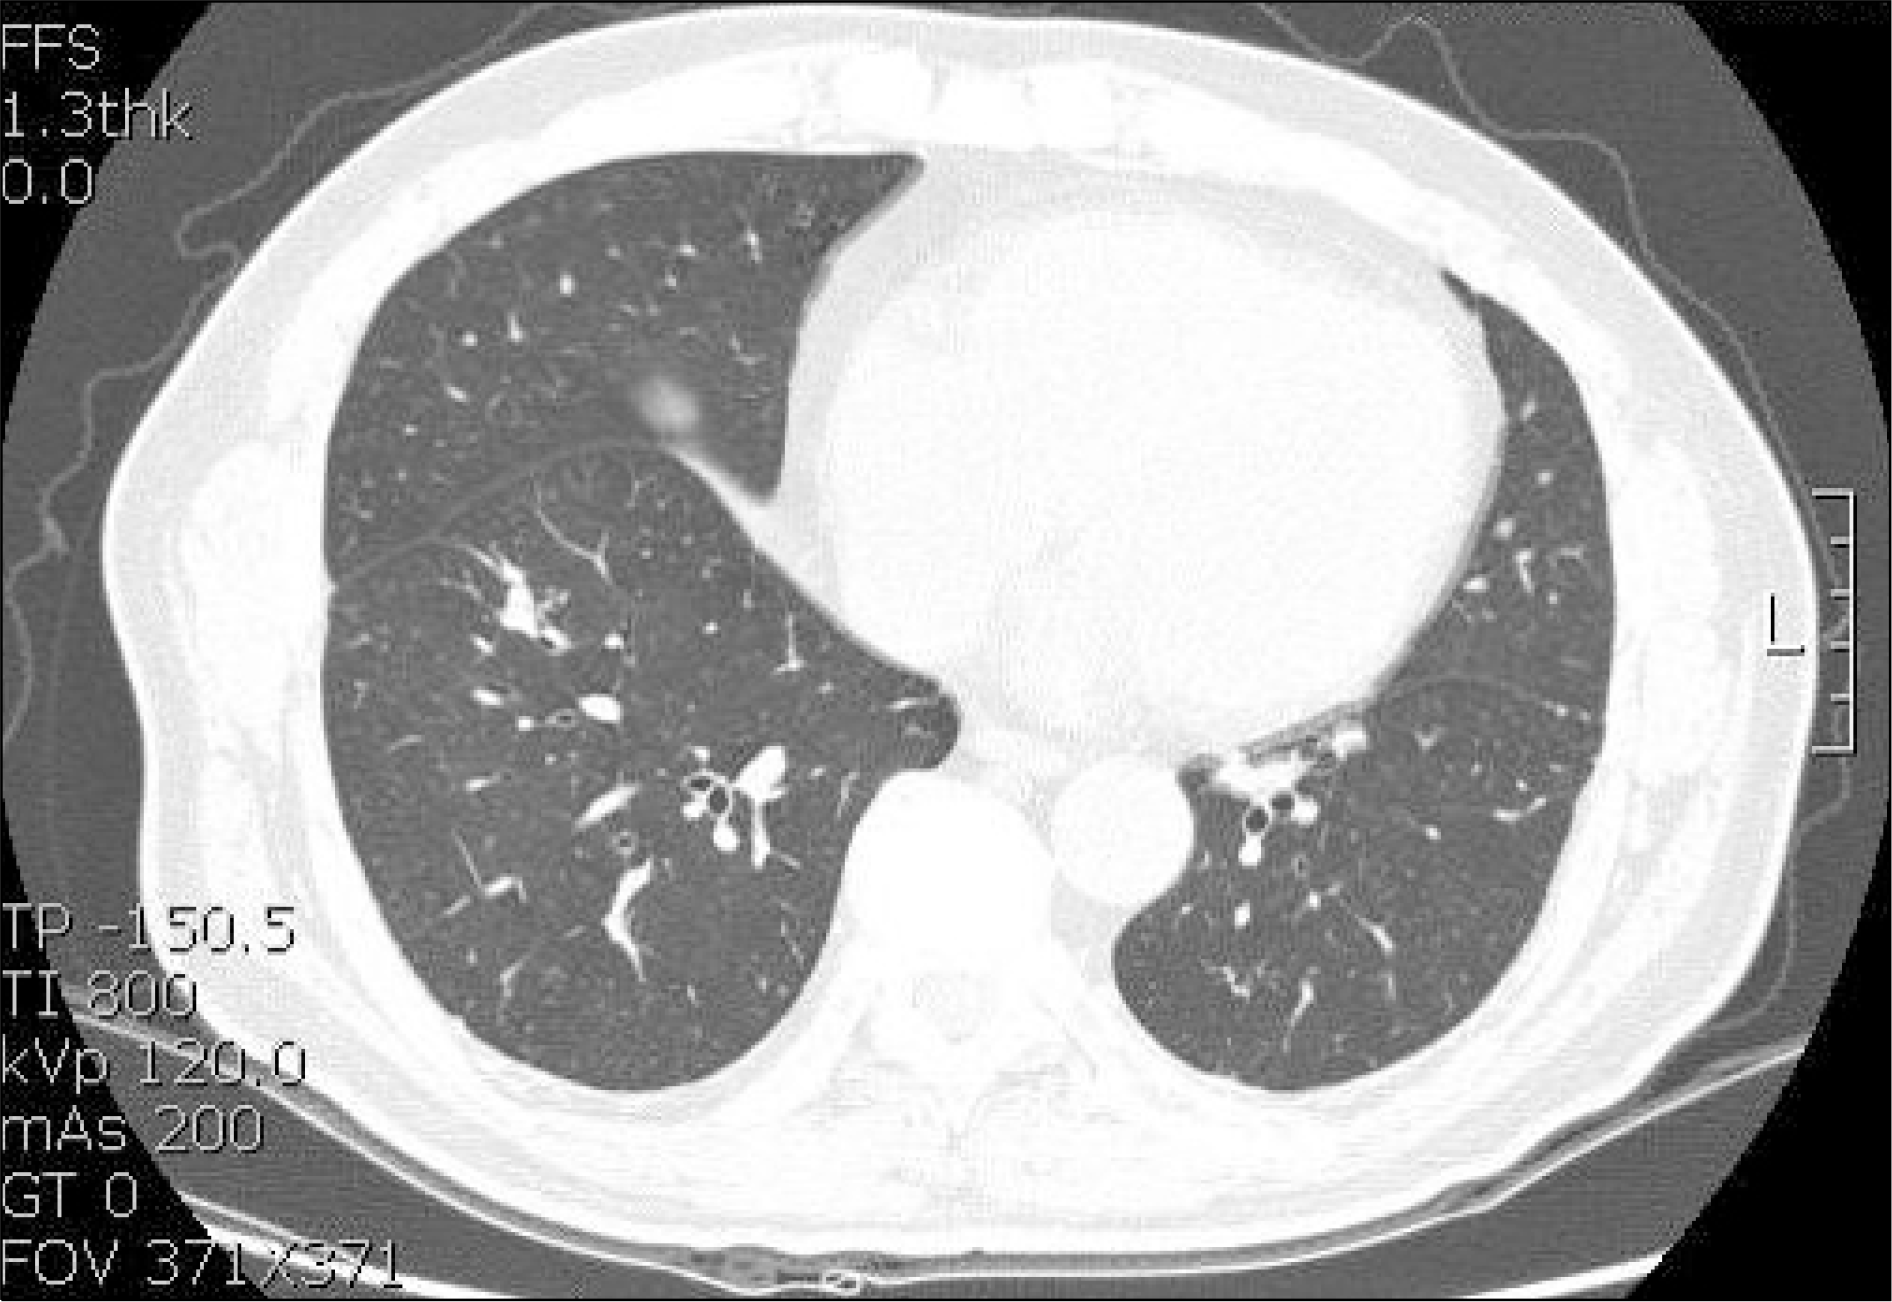

Fig. 1.

Initial chest CT scan showing branching opacities with tree-in-bud appearance consistent with tortuous pulmonary arteriolar dilatation by tumor embolism in both lungs.